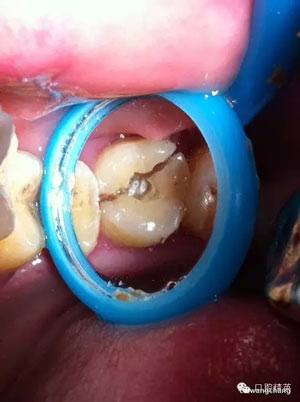

牙劈裂修復病例

上圖可見該患者的牙斜向裂開,同時沒有做完善的根管治療

先給與根管充填(前提是無根管劈裂),牙膠截斷于根管口

頰部預備溝槽,準備結扎絲復位,現(xiàn)已改為成型夾或血管鉗鉗夾復位